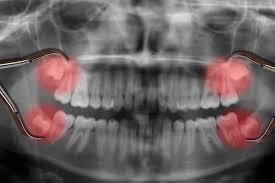

1. Răng khôn mọc lệch, mọc ngầm

Đây là tình trạng rất thường gặp. Răng khôn không đủ chỗ mọc thẳng sẽ bị kẹt trong xương hàm hoặc mọc nghiêng vào răng số 7 bên cạnh.

Bước 2: Chụp phim X-quang kiểm tra vị trí răng khôn

Đây là bước rất quan trọng giúp:

- Xác định chính xác vị trí và hướng mọc của răng khôn.

- Đánh giá khoảng cách đến các cấu trúc quan trọng như răng số 7, xoang hàm, dây thần kinh.

- Lập kế hoạch nhổ răng an toàn, hạn chế tối đa biến chứng.